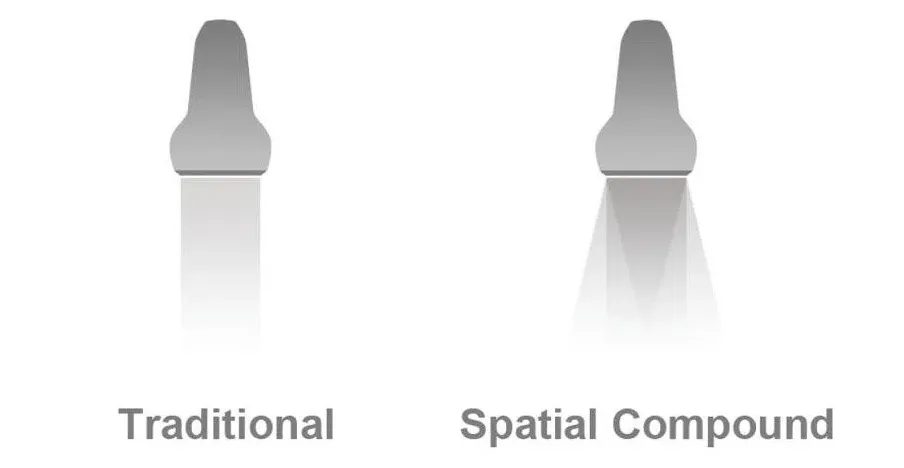

Spatial Compound Imaging (SCI)

Пространственный компаундинг, визуализация с пространственным совмещением. Технология сложно-составного мультилучевого сканирования основана на методе формирования составного изображения разнонаправленными ультразвуковыми лучами. Таким образом, объект облучается с разных направлений, нивелируя разного рода артефакты. С помощью этого режима можно избежать теней за эхоплотными структурами, снизить спекл-шум и эффекты переотражений за ближней стенкой в крупных сосудах.